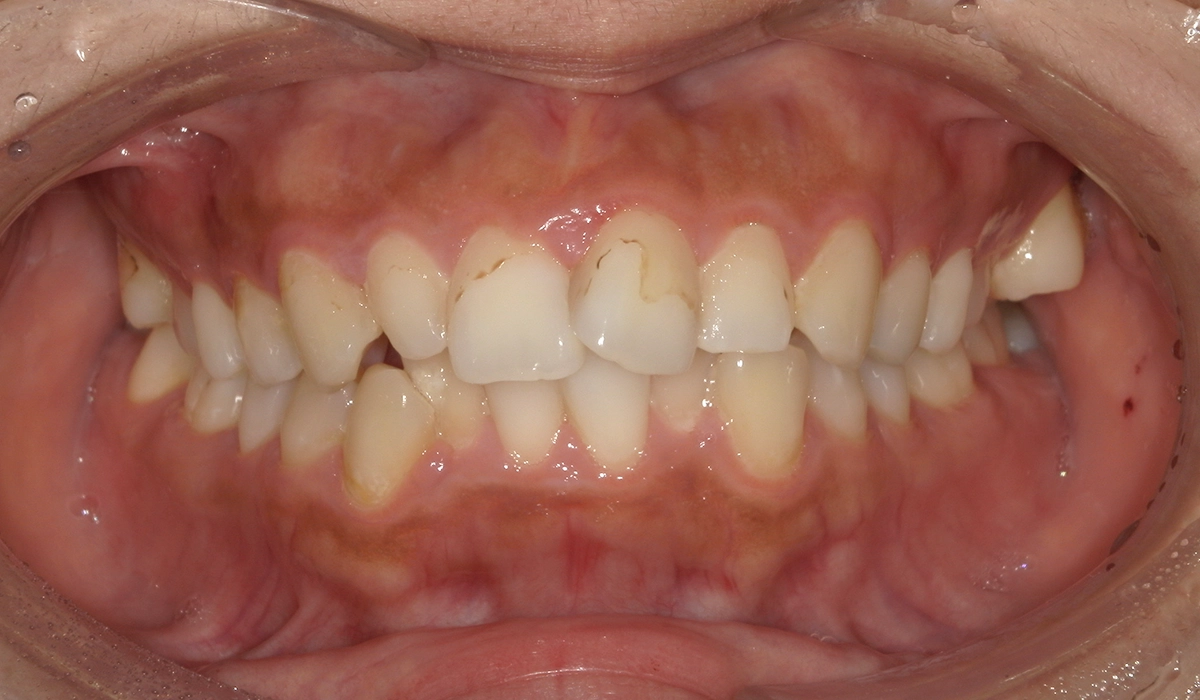

今回ご紹介する患者様は、上下の歯並びのガタツキを気にされており、矯正検査後叢生Ⅱ級と診断いたしました。

術前:正面

術後:正面